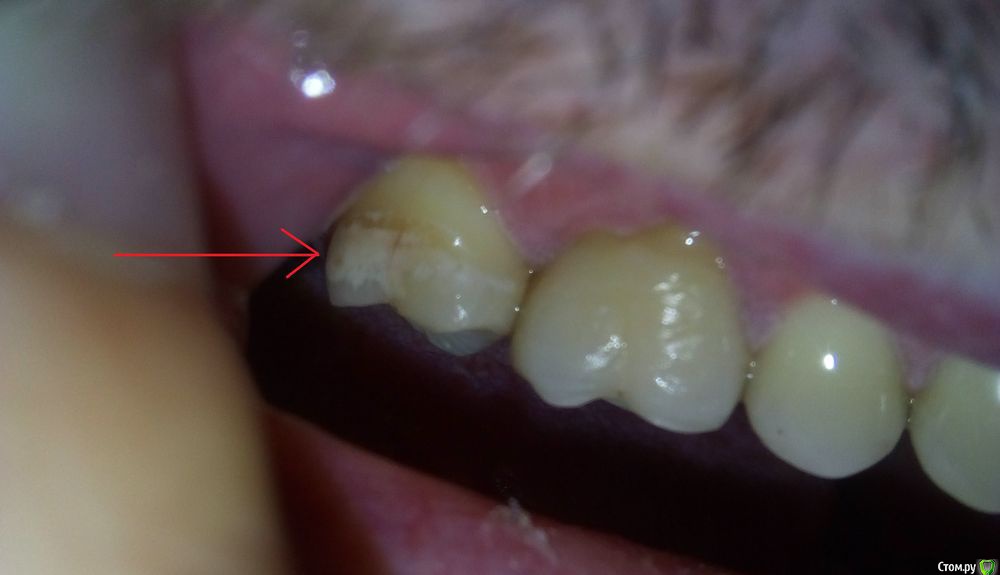

usilitel Опубликовано 17 ноября, 2018 Поделиться Опубликовано 17 ноября, 2018 (изменено) После замены пломбы в верхней 7-ке зуб окрасился и стал довольно сильно реагировать на холодное.Перед перепломбировкой 7-ки зуб иногда болел в области корней, после перепломбировки боли не прошли, плюс добавилась реакция на холодное. Вопросы: 1) Нормально ли, что зуб окрасился после перепломбировки?2) Может ли быть причина окраски в том, что зуб "отравлен" из-за токсичности пломбы в соседнем зубе? Снимок 1 ПОСЛЕ перепломбировки 7-ки: Снимок 2 ПОСЛЕ перепломбировки 7-ки: Рентгеновский снимок ДО перепломбировки 7-ки: Рентгеновский снимок ПОСЛЕ перепломбировки 7-ки - отсутствует. Моя версия (я не профессионал, так что сужу по собственным ощущениям):1,5 года назад при замене пломбы в соседней 6-ке пломбу скорее всего недосветили, и это сделало пломбу токсичной для зуба.1 год назад в 6-ке запломбировали каналы, но стало еще хуже (появилась невралгия, зуб реагирует при постукивании, зуд в области корней, болит глаз, стреляет в висок). При этом 6-ку удалять никто не хочет, т.к. на снимках всё более-менее нормально. Я думаю что из-за токсичности пломбы воспалились ткани вокруг 6-го зуба.Дальше это отравление в 6-ке перекинулось на 7-ку, и 7-ка тоже стала "отравленной". Из-за этого при замене пломбы 7-ка окрасилась и стала реагировать на холодное.Повторюсь - это моё непрофессиональное мнение, сужу по собственным ощущениям. Изменено 17 ноября, 2018 пользователем usilitel Ссылка на комментарий

red_butler Опубликовано 17 ноября, 2018 Поделиться Опубликовано 17 ноября, 2018 Ничего не окрасилось, это кариес в стадии пятна Ссылка на комментарий